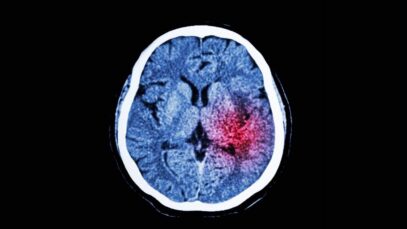

A recent survey conducted by an Auckland University of Technology lecturer has found that a Stroke is a serious health condition especially amongst the Pasifika community.

The survey conducted by Dr. Felicity Bright,a Senior Lecturer in Rehabilitation, published in the New Zealand Medical Journal, aims to identify social factors, issues and inconsistencies in support for people who have suffered from a stroke.